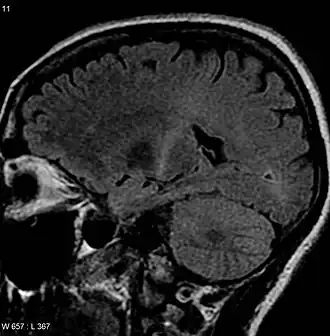

RMN cu semnal crescut(ă) în partea posterioară a capsulei interne ce poate fi trasată către cortexul motor în concordanță cu diagnosticul de SLA.